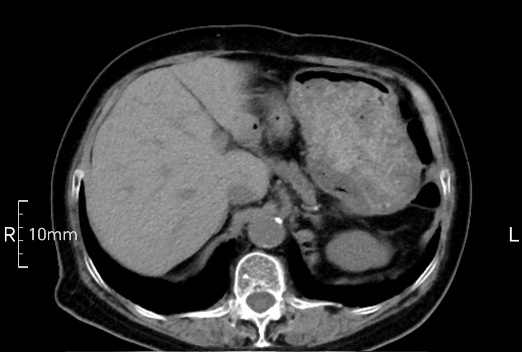

沒禁食,胃內全是食物,導致胃壁顯示不清。

禁食但檢查前沒有喝飽,胃未能漲開,胃壁觀察效果不佳。

完美禁食且喝飽飽,胃壁完美展現。